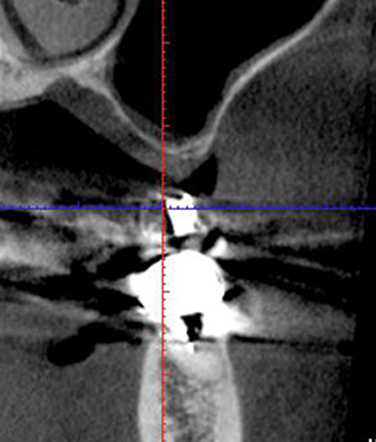

骨が一番薄いところで約2mm程度しかありません。通常であれば、サイナスリフトをして6ヵ月後にインプラント埋入を行いますが、当院では 2mmの骨があればインプラントを同時に埋入します。そうすることで治療期間を6ヶ月以上短縮することができます。

埋入部位のCT像 残存骨は2ミリもありません。